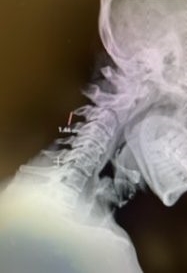

(2a) Lateral Flexion cervical x-rays demonstrating 8mm of splaying of the C34 interspinous distance

The fluid was possibly consistent with CSF versus chronic hematoma. The patient was also noted to have a high signal within the interspinous space of C3-C4. This high signal was consistent with a ruptured C3-4 interspinous ligament. Cervical flexion-extension x-rays demonstrated 6 mm of widening of the C3-4 interspinous space on flexion x-ray consistent with cervical instability (Fig. 2a and 2b).